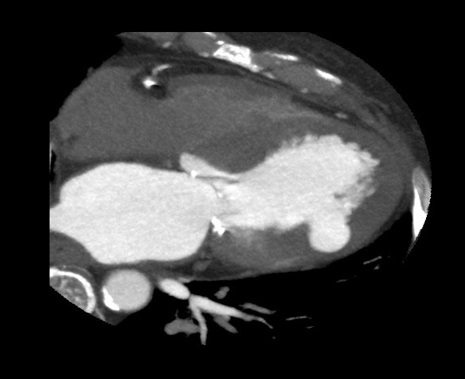

An asymptomatic 75-year-old female with past medical history of percutaneous coronary intervention for angina pectoris and chronic renal failure on hemodialysis was referred to our department for the management of left ventricular aneurysm which was pointed out on the follow-up echocardiography. Coronary angiography showed no restenosis of the stent site but 100% stenosis of distal segment of left circumflex artery which had not been detected previously. Echocardiography showed an abnormal cavity that communicated with the left ventricle through a small hole, 2cm in diameter in the lateral wall (Figure 1). Figure 2. Computed tomography scan showed an aneurysm in the lateral wall of left ventricle without pleural effusion (Figure 2). Magnetic resonance imaging showed an aneurysm with abrupt discontinuing of myocardium and narrow neck (Figure 3). Pseudoaneurysm, subepicardial aneurysm or pseudo-pseudoaneurysm was thought as differential diagnosis. Aneurysmectomy and patch closure was planned. Surgery was performed via medial sternotomy. Cardiopulmonary bypass (CPB) was carried out with cannulation of the aorta and the right atrium under cardiac arrest and mild hypothermia. Macroscopically, a subepicardial little red aneurysmal site with a weakened wall was seen at the apical part of the left ventricle. Sign of rupture, adhesion to the surrounding structures or pericardial effusion was not seen. The aneurysmal sac was opened and a sclerotic wall was seen. There was a narrow neck at the base of the incised aneurismal sac communicating with the left ventricular cavity. Myocardium was not contained in the aneurysm cavity (Figure 4). Following the resection of the aneurysm, the defect was patch closed with Gelweave graft.  Two Teflon pledgets were used to reinforce the ventricle suture on the outside. The weaning from CPB and postoperative course were uneventful.

Figure 2. Computed tomography scan showed an aneurysm lying below the inferior surface of left ventricle without pleural effusion.